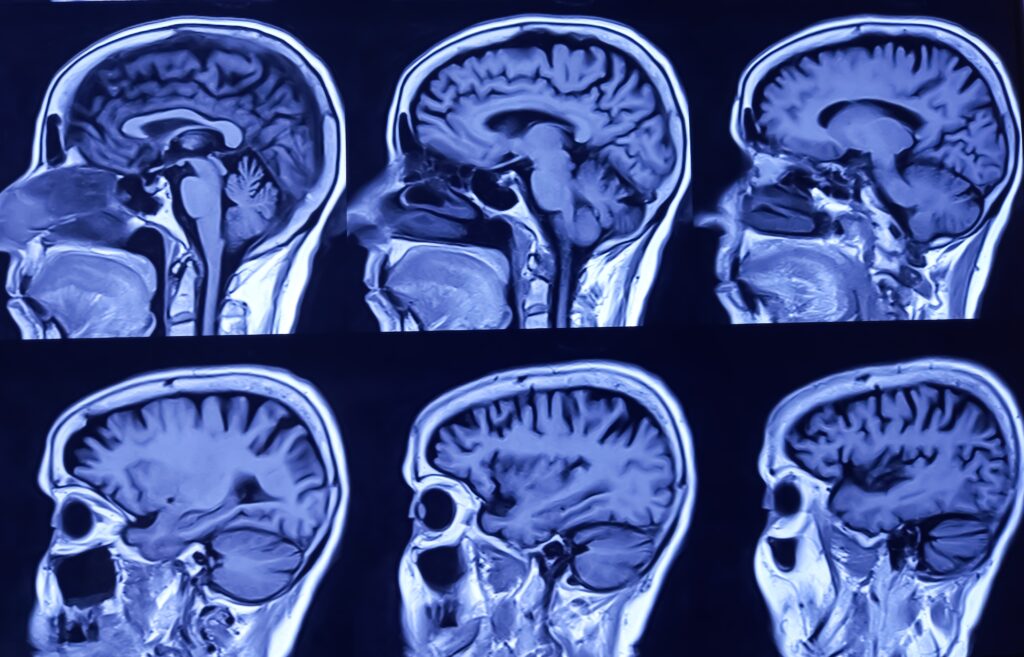

The research, based on brain scans from nearly 4,000 people ranging from infancy to age 90, shows that brain development does not happen gradually over time but instead shifts through distinct “epochs” with major changes in structure and connectivity.

During childhood, the brain undergoes “network consolidation,” where excess neural connections are trimmed and more useful ones are strengthened. Although grey and white matter grow rapidly during this time, the overall efficiency of brain wiring actually decreases.

In the adolescent phase, white matter continues to grow and brain networks become more refined. Connectivity efficiency steadily improves, which is linked to better thinking and cognitive performance. Researchers say this period is also when many mental health conditions begin to emerge.

The biggest structural shift happens around age 32, when the brain moves into its longest-lasting adult phase. During this period, brain organisation stabilises, and regions become more compartmentalised. This phase is linked to relative stability in intelligence and personality.

From around age 66, and more markedly after 83, brain connectivity begins to decline, likely reflecting age-related changes and degeneration in white matter.